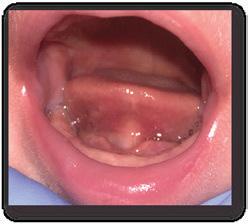

There Is Only One Smile That Matters. Yours!

You are in good hands! Dr. Makarita is the only accredited Fellow of the American Academy of Cosmetic Dentistry in Virginia.

BEFORE AFTER

At Tysons Aesthetic Dentistry Dr. Makarita has designed and equipped his practice with your smile in mind. Dedicated care and attention are just the beginning.

As a general dentist with a passion for aesthetic and cosmetic dentistry, whether a simple filling or a smile makeover, Dr. Makarita’s priority is to help you love your smile.

Since earning his doctorate from the Medical College of Virginia, Dr. Makarita has continually upgraded his skills and knowledge with continuing education so he can always bring you the most advanced options for all your dental needs.

Always welcoming new patients! Call 703-532-2020  8150 Leesburg Pike | Suite 503, Vienna VA 22182 www.ilovethatsmile.com

FREE SMILE EVALUATION In person or visit website for virtual smile consultation

Dr. H.R. Makarita

Accredited Fellow, American Academy of Cosmetic Dentistry

Master, Academy of General Dentistry

Master, International Congress of Oral Implantologists

Master, Las Vegas Institute for Advanced Dental Studies

to Love Your Smile? Dr. Makarita would love to meet you! About